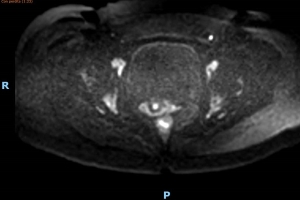

La tabella 2 descrive la presenza del segnale nella parete vescicale anteriore con la DW-MRI (Fig. 1), il segnale è stato rilevato in 15 pazienti con BPS-IC su 22, che corrispondono al 68,18% dei pazienti con con BPS-IC, rispetto a 3 su 20 pazienti nel gruppo di controllo, ovvero una positività del 15%. Il valore P = .005 conferma la significatività statistica di questa differenza.

Tabella 2 Confronto tra pazienti con CI e senza CI in base alla localizzazione del segnale rilevato dalla DW-MRI sulla parete vescicale anteriore.

Segnale DW-MRI - parete vescicale anteriore no IC IC totale

Segnale assente

17

85%

7

31.82%

24

Segnale presente 3

15%

15

68.18%

18

Totale 20 22 42

Fig. 1 DW-MRI.  Il segnale presente sulla parete vescicale anteriore in paziente con CI (versione a colori disponibile online).